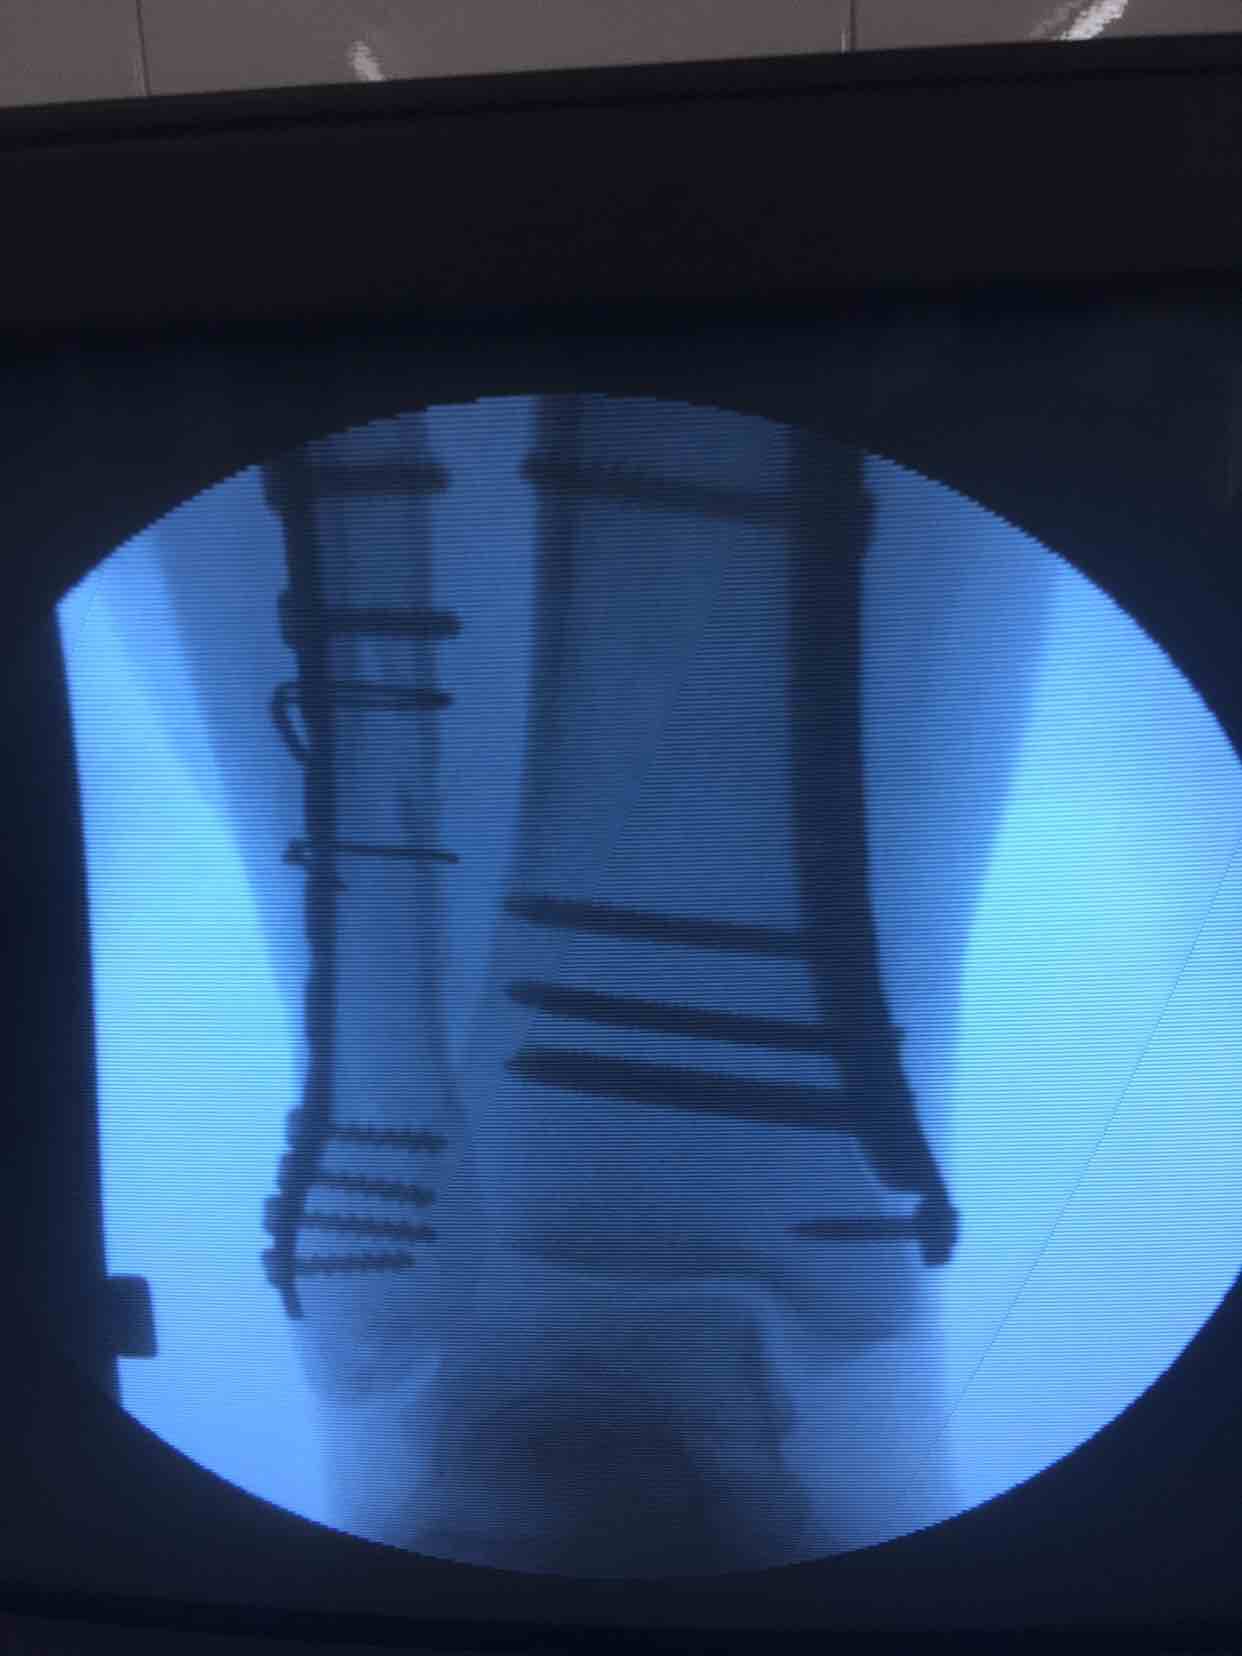

诊断右胫腓骨粉碎性骨折

在腰麻下行切开复位内固定术,术后抗炎,消肿等处理。